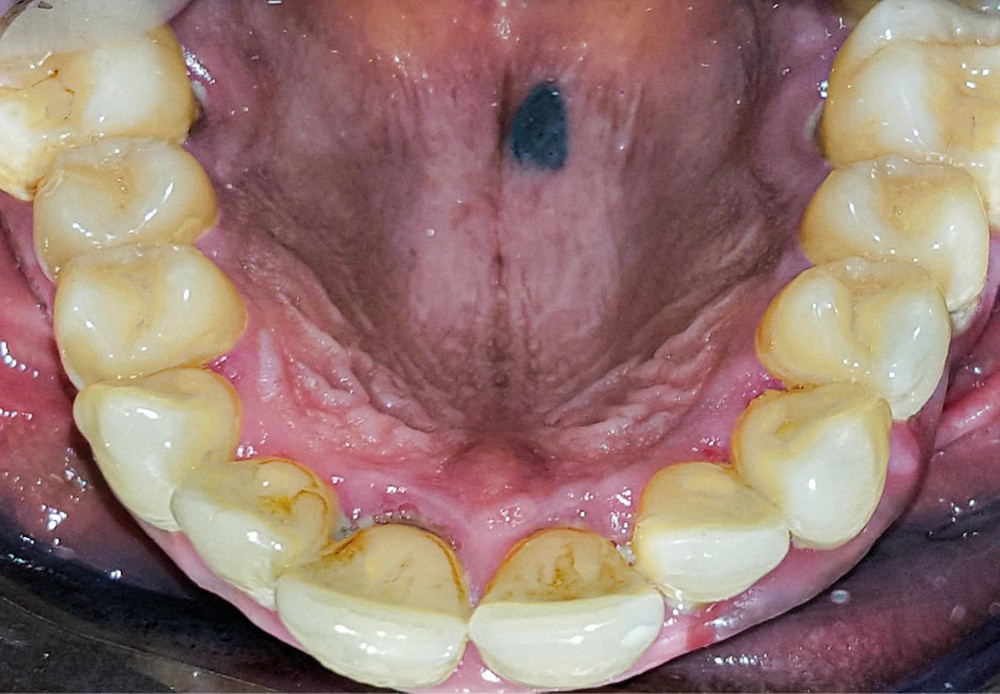

Anamnèse. Un patient adulte est adressé par son chirurgien-dentiste traitant après la découverte fortuite d’une lésion palatine. Il est en bonne santé générale, ne fume pas, consomme de façon occasionnelle des boissons alcoolisées, ne présente aucun antécédent médical et ne prend aucune médication. En outre, il ne ressent aucune douleur ni autre symptôme général. Par ailleurs, son phototype cutané est de type V selon la classification de Fitzpatrick (peau, cheveux et yeux de couleur foncée [1]).

• la présence d’une macule pigmentée, de couleur noire-bleutée (contrastant avec les plages pigmentées physiologiques), bien délimitée, aux contours nets, située dans la muqueuse postérieure du palais dur à droite du raphé ;

• L’absence de lésion pigmentée d’aspect similaire sur les autres muqueuses orales, les parties cutanées visibles (visage, mains, bras) et les ongles des doigts de la main.